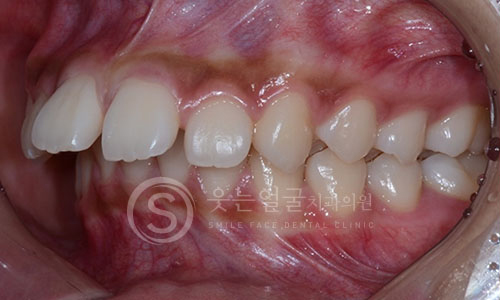

한눈에 보는

임플란트 전후사진